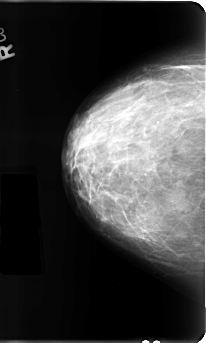

ics_version 1.0 filename B-3111-1 DATE_OF_STUDY 23 7 1996 PATIENT_AGE 44 FILM FILM_TYPE REGULAR DENSITY 3 DATE_DIGITIZED 22 1 1998 DIGITIZER LUMISYS LASER SEQUENCE LEFT_CC LINES 4888 PIXELS_PER_LINE 2856 BITS_PER_PIXEL 12 RESOLUTION 50 OVERLAY LEFT_MLO LINES 4864 PIXELS_PER_LINE 3040 BITS_PER_PIXEL 12 RESOLUTION 50 OVERLAY RIGHT_CC LINES 4792 PIXELS_PER_LINE 2880 BITS_PER_PIXEL 12 RESOLUTION 50 NON_OVERLAY RIGHT_MLO LINES 4824 PIXELS_PER_LINE 2960 BITS_PER_PIXEL 12 RESOLUTION 50 NON_OVERLAY |